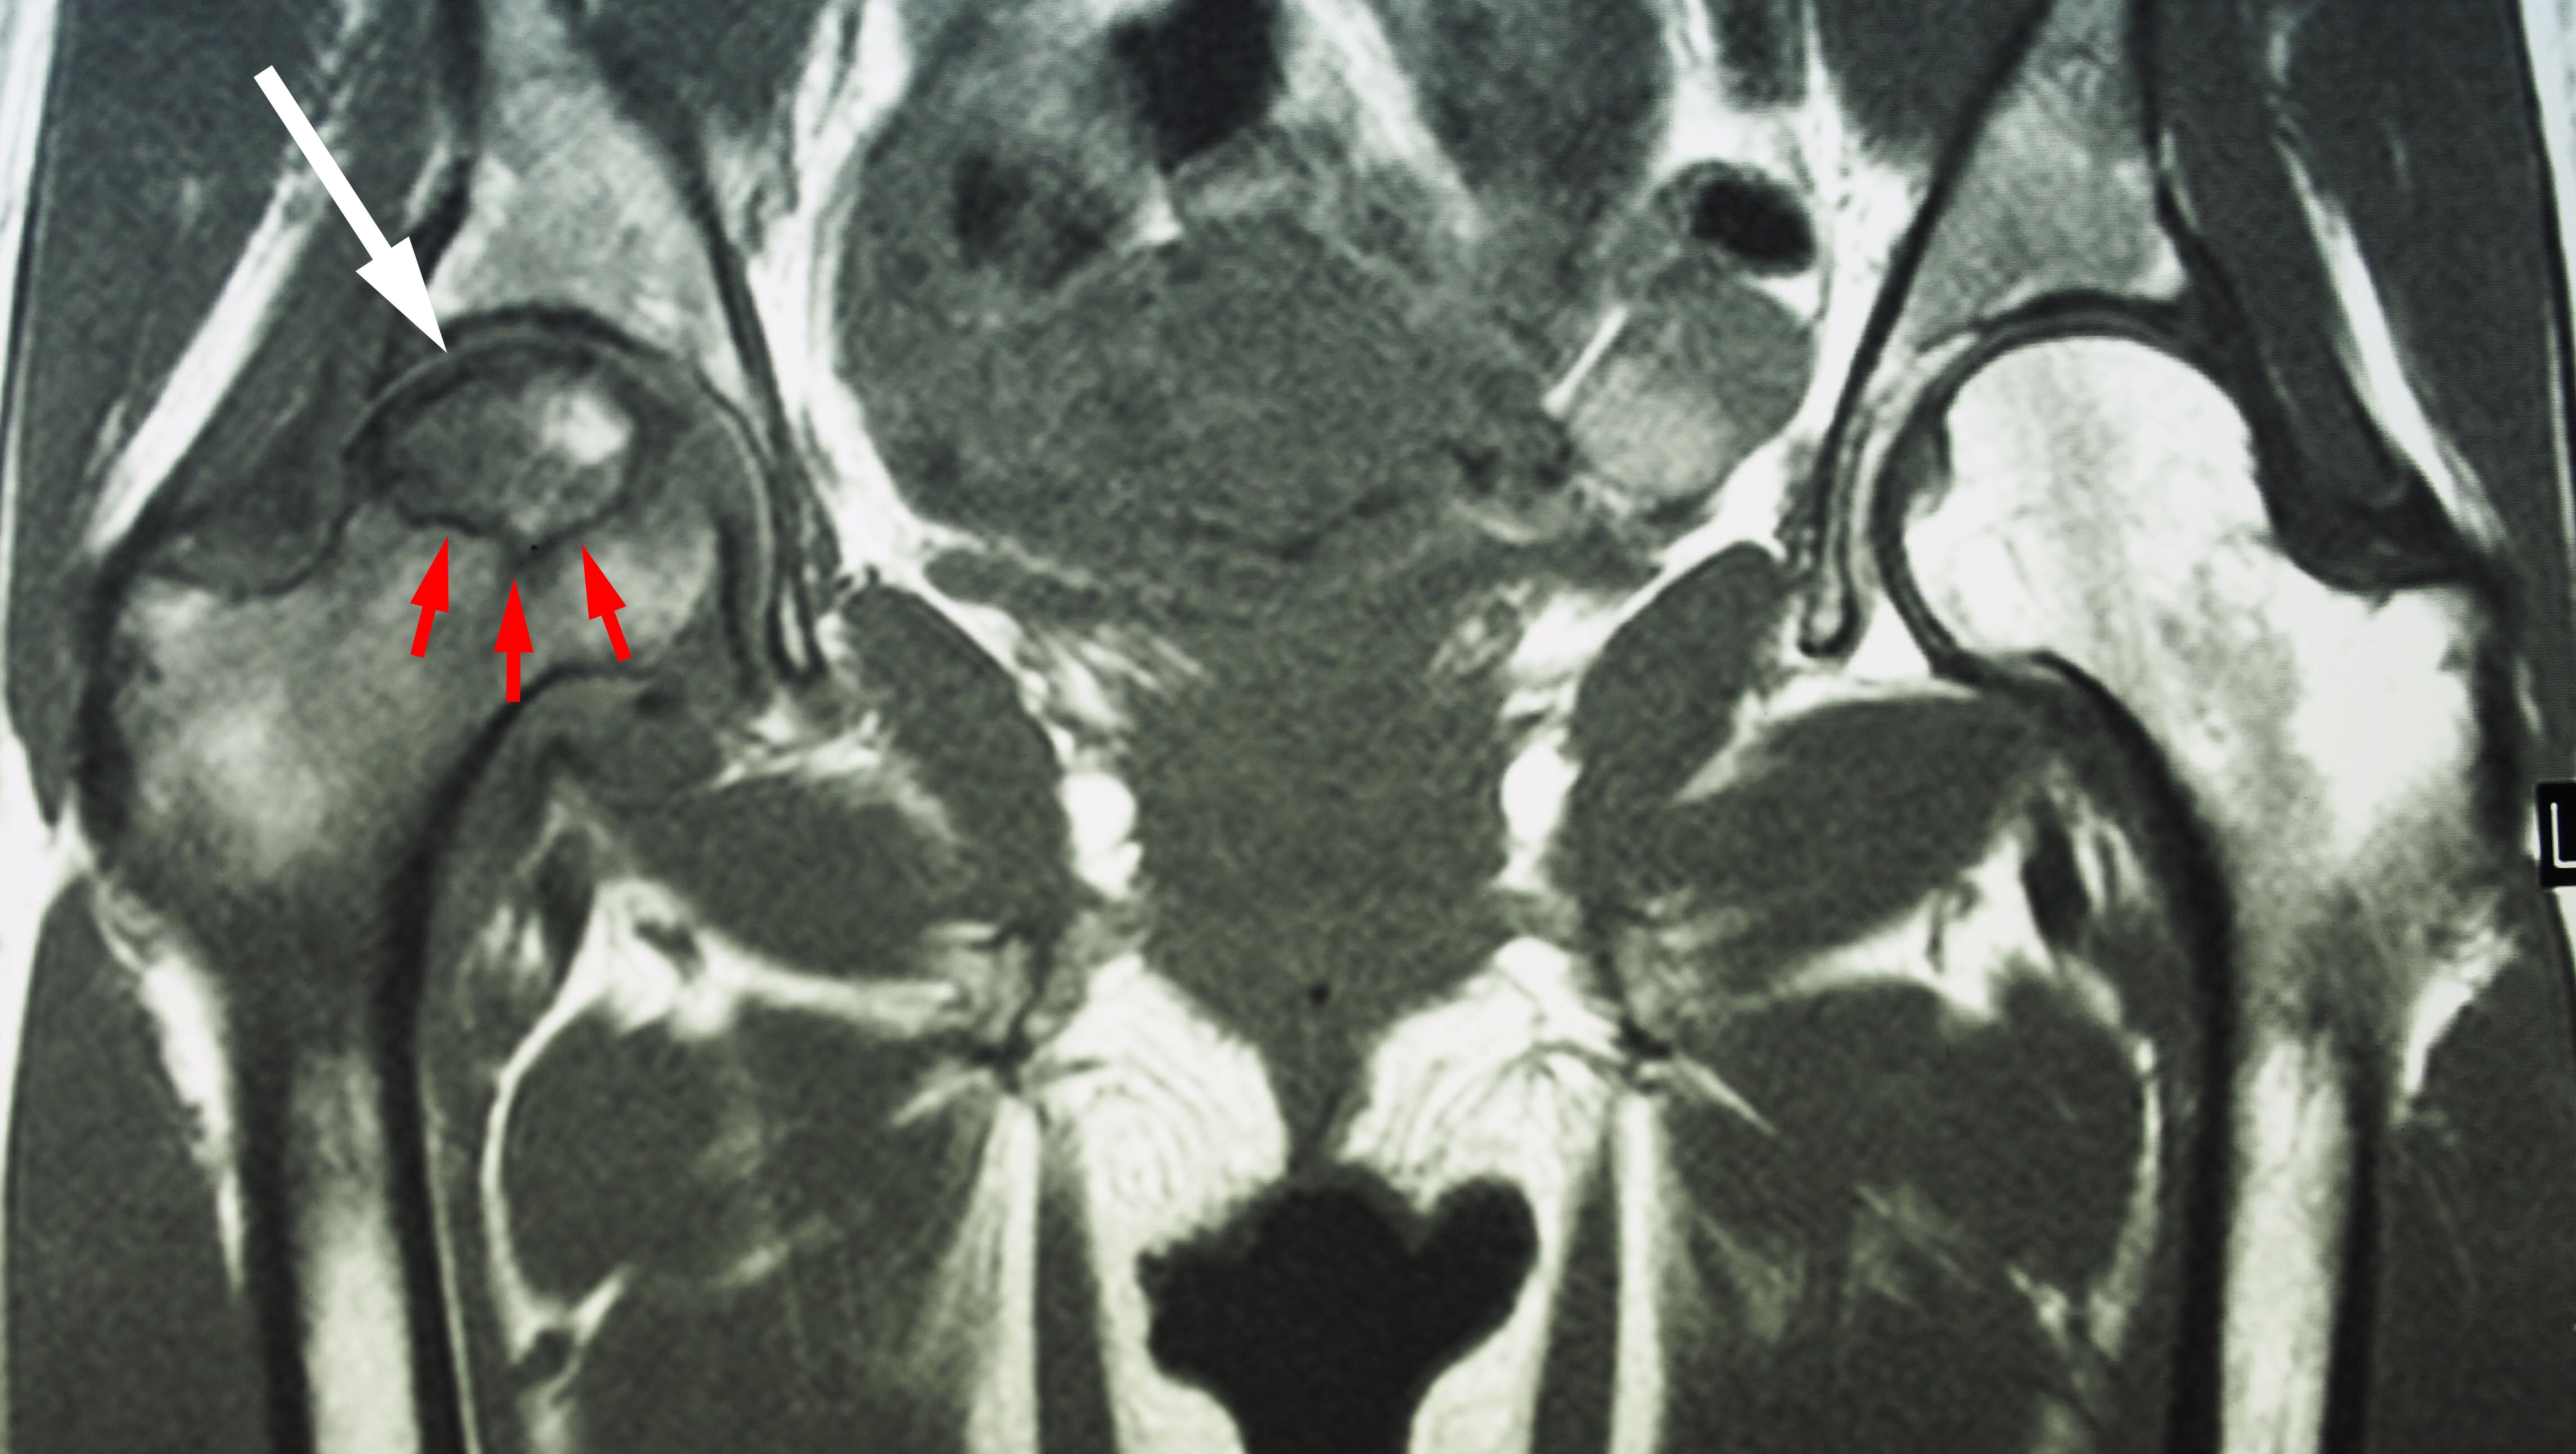

Magnetic resonance imaging (MRI) scans - Early changes in the bone that may not show up on an x-ray can be detected with an MRI scan. These scans are used to evaluate how much of the bone is affected by the disease. An MRI may also show early osteonecrosis that has yet to cause symptoms (for example — osteonecrosis that may be developing in the opposite hip joint).

This MRI scan shows osteonecrosis in a patient’s right hip (white arrow). The dark line (red arrows) denotes the border between dead bone and living bone. The patient's left hip is normal.